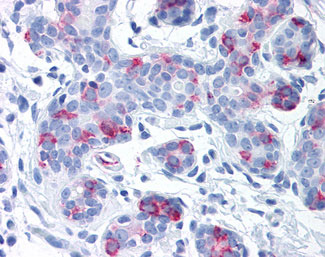

Anti-WNT8A antibody APR02104G IHC of human breast. |